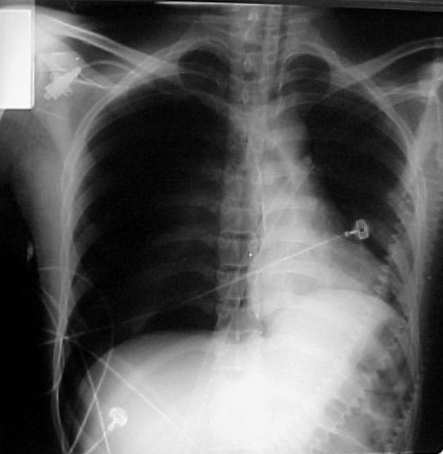

TCCC and most EMS protocols list needle thoracostomy as the intervention of choice in the management of a suspected tension pneumothorax.

Finger thoracostomy is the approach employed by some Australian HEMS services in traumatic arrest resuscitation. Finger thoracostomy is similar in principle to chest tube insertion, however, no tube is inserted. Instead, an incision is made in the chest wall and the finger inserted, performing blunt dissection through the parietal pleura. The finger is then removed with nothing remaining in the incision. The creation of a vent to the outside environment combined with positive pressure ventilation prevents the accumulation of air in the pleural space.